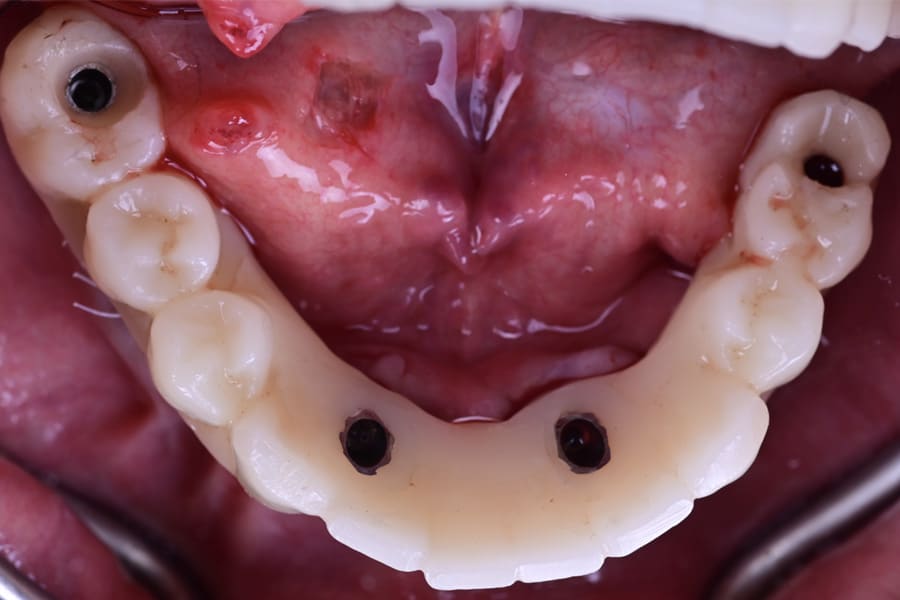

During surgery, flapless osteotomies were prepared under guided conditions. All implants achieved insertion torque values sufficient for immediate loading. Multi-unit abutments were connected, and the PMMA provisionals were relined intraorally, ensuring passive seating. Occlusion was carefully adjusted to light centric contacts and shallow lateral guidance, minimizing overload during early osseointegration (Figure 18 and Figure 19).

The patient functioned with provisionals for 12 weeks. Soft tissues matured around the prosthetic contours, and minor esthetic refinements were noted (Figure 20).